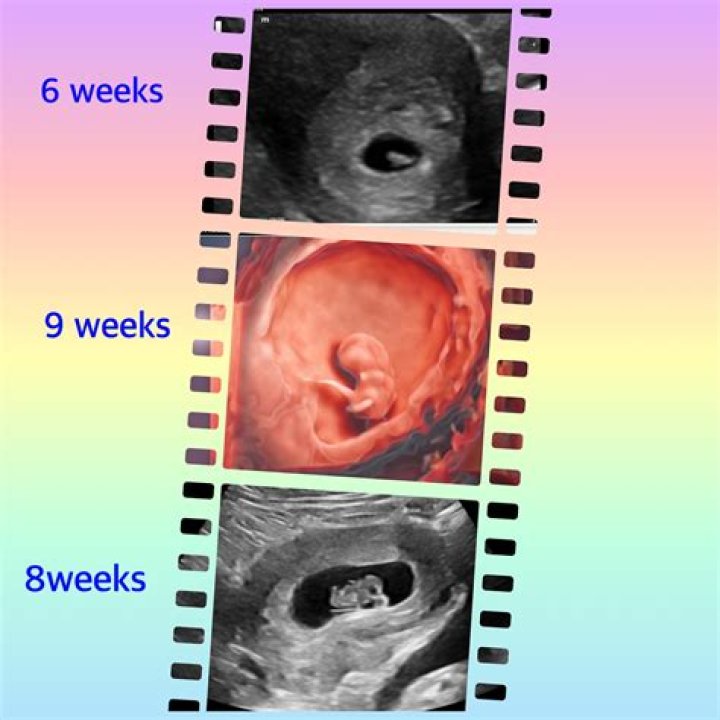

How soon should you see an OB-GYN when pregnant?

The first prenatal appointment usually takes place in the second month, between week 6 and week 8 of pregnancy. Be sure to call as soon as you suspect you're pregnant and have taken a pregnancy test. Some practitioners will be able to fit you in right away, but others may have waits of several weeks (or longer).